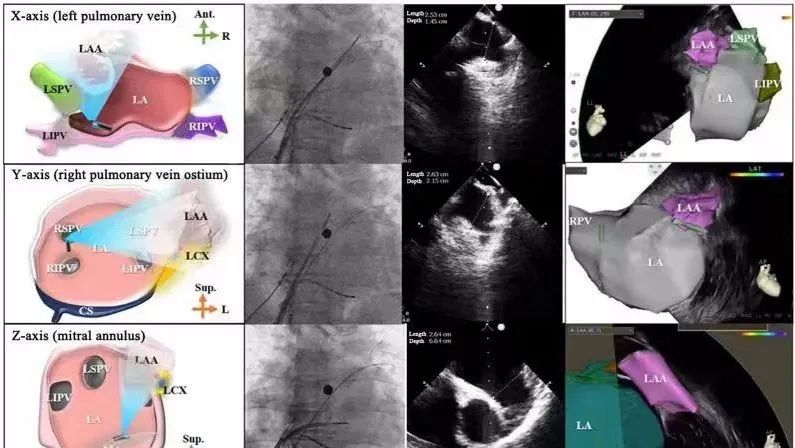

一種與心導(dǎo)管檢查相結(jié)合的超聲心動(dòng)圖診斷新興技術(shù),通過將超聲探頭置于心腔內(nèi)部,發(fā)射并接收超聲信號(hào),來精確獲取心臟解剖結(jié)構(gòu)、心臟血流動(dòng)力學(xué)等信息的實(shí)時(shí)成像。與其他影像技術(shù)相比,ICE技術(shù)具有操作簡單、無輻射、安全性高、手術(shù)效率高、實(shí)用等優(yōu)勢(shì),ICE在很大程度上有望取代經(jīng)食道超聲心動(dòng)圖(TEE),成為電生理和結(jié)構(gòu)性心臟病領(lǐng)域的理想成像方式。

目前ICE技術(shù)已被應(yīng)用于左心耳封堵、房顫射頻消融、二尖瓣成形、房間隔缺損封堵等多種心臟介入手術(shù),應(yīng)用場景主要圍繞心臟電生理、結(jié)構(gòu)性心臟病等領(lǐng)域,目前以電生理應(yīng)用為主。數(shù)據(jù)顯示,我國結(jié)構(gòu)性心臟病介入器械市場規(guī)模已從2017年的4億元增長至2021年的20億元,年復(fù)合增長率達(dá)48.3%;預(yù)計(jì)到2025年,該市場規(guī)模將達(dá)到104億元,可以預(yù)見ICE市場規(guī)模也將同步高速增長,未來市場發(fā)展空間廣闊。

心腔內(nèi)超聲(ICE)技術(shù)壁壘極高,國內(nèi)主要廠商核心部件仍舊為進(jìn)口,集成了超聲和圖像處理最前端技術(shù),包括超聲探頭、線纜、軟件成像算法等,是當(dāng)前內(nèi)窺超聲方向最具挑戰(zhàn)的領(lǐng)域。ICE的應(yīng)用經(jīng)歷了2D平面成像、3D三維立體成像、以及4D的實(shí)時(shí)三維立體成像階段。